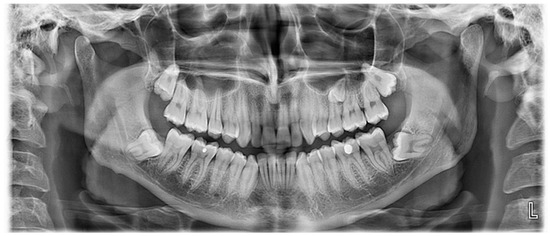

2.2. Case 2

Case 2 Presentation